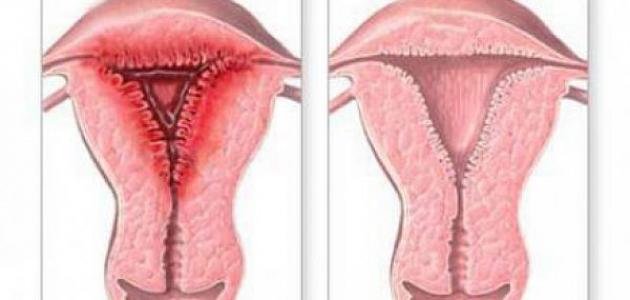

التهابات الرحم أو التهاب بطانة الرحم (بالإنجليزية: Endometritis) هي إحدى المشاكل الصحية التي تصيب بطانة الرحم وتؤدي إلى التهابها، ويكون الالتهاب في هذه الحالة ناجمًا عن العدوى، ويُشار أنّ التهاب بطانة الرحم يختلف عن الانتباذ البطانيّ الرحميّ أو ما يعرف ببطانة الرحم المهاجرة (بالإنجليزية: Endometriosis)؛ فعلى الرغم من كونهما اضطرابين يؤثران في بطانة الرحم إلّا أنّ الانتباذ البطانيّ الرحميّ لا يكون ناجمًا عن الإصابة بالعدوى؛ وإنما عن نمو بطانة الرحم خارج الرحم، والذي ينجم عنه الشعور بألم في منطقتي البطن والحوض،[١] أما الأعراض المرافقة لالتهاب بطانة الرحم؛ فتتضمن ما يأتي:[٢][٣]

وجد أن الإصابة بالتهاب بطانة الرحم لها دورٌ في التأثير في قدرة المرأة على الحمل أو حتى استمرار الحمل في حال حدوثه؛ إذ يشار إلى أن التهابات الرحم قد تؤدي إلى تشكّل الندب، الذي يمنع الجنين من الانغراس أو التطور بشكلٍ طبيعيّ داخل بطانة الرحم، وفي هذا السياق يجدر الذكر أنّ الطبيب المختص بعلاج اضطرابات الخصوبة قد يطلب إجراء فحص للكشف عن إصابة المرأة بالتهاب بطانة الرحم أو يصف لها العلاج المناسب في حال اكتشاف الإصابة، خاصةً في الحالات التي تُعاني منها المرأة من الإجهاض المتكرر، أو الفشل المتكرر لعملية التلقيح الاصطناعي أو ما يعرف بالإخصاب في المختبر (بالإنجليزية: In vitro fertilization) واختصارًا IVF على الرغم من الجودة العالية للأجنّة المستخدمة،[١] فقد بينت دراسة نشرت في مجلّة الطب التناسليّ السريريّ والتجريبيّ (بالإنجليزية: Clinical and experimental reproductive medicine) عام 2016 أنّ الإصابة بالتهاب بطانة الرحم المزمن قد تؤثر في الخصوبة لدى المرأة بطريقتين وهما: منع البويضة الملقّحة من الانغراس في بطانة الرحم كما ذكر سابقًا وارتفاع احتمالية حدوث الإجهاض المتكرّر،[١][٤] وقد أشارت دراسة أخرى تمّ نشرها في المجلة الأمريكيّة لعلم المناعة الإنجابيّة (بالإنجليزية: American journal of reproductive immunology) عام 2018 إلى أنّ ما يزيد عن 50% من النساء اللواتي يعانين من مشاكل في الخصوية يعانين من التهاب بطانة الرحم المزمن، وأنّ خضوعهنّ للعلاج بالمضادّات الحيويّة أدّى إلى انخفاض نسبة الأعراض لديهن بما يزيد عن 80%، وبالتالي ارتفعت لديهن نسبة حدوث الحمل والولادة.[١][٥]